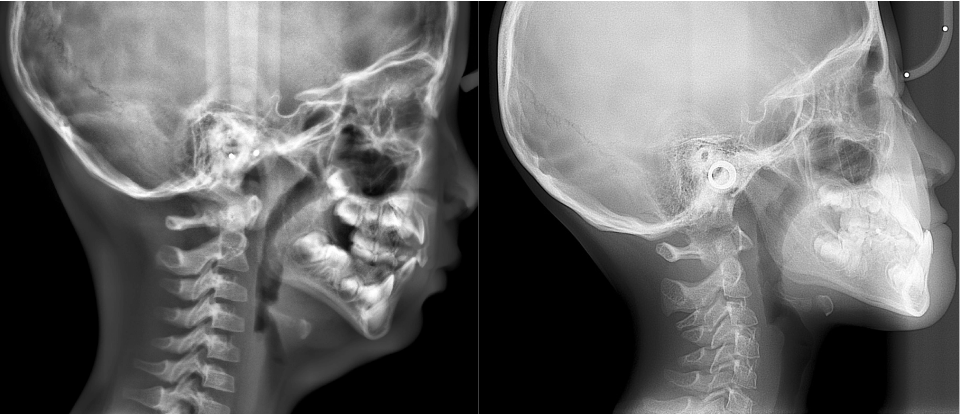

可以考虑带孩子面诊正畸医生检查,通过拍摄头颅侧位片和牙齿全景片,检查上下颌骨发育情况,以及萌出和未萌出恒牙的位置、大小和形态,结合孩子实际面型和口内情况,确定适合孩子的方案。